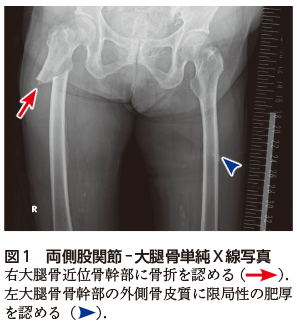

• A1:右大腿骨近位骨幹部に転位を伴う骨折を認める(図1図2A).左大腿骨骨幹部の外側骨皮質に限局性の肥厚を認める(図1図2B).

X線写真において,不全骨折の段階では大腿骨外側皮質にbeakingやflaringと呼ばれる限局性の肥厚を認める.完全骨折では外側骨皮質に端を発した骨を横断する骨折線を認める.ビスホスホネート製剤を長期内服中の患者で疼痛などの前駆症状の訴えがあるが,X線写真で診断がはっきりしない場合は,CT,MRI,骨シンチグラフィでの精査を考慮する.完全骨折を認める場合は外科的な治療を行う.以前は不全骨折に対しても外科治療が選択されていたが,近年ではビスホスホネート製剤を中止し,患肢への荷重を制限することで保存的に治療される.ただし,骨折が進行する場合や持続的な疼痛がある場合には,外科的治療が適応となる.このような治療方針のため,不全骨折の段階で指摘することは,患者のQOLを維持するうえで重要である2).今回の症例のように片側の非定型大腿骨骨折を認める場合は,対側にも非定型大腿骨不全骨折の画像所見がないか,外側骨皮質の肥厚に注意を払うことが大切である1)

図2